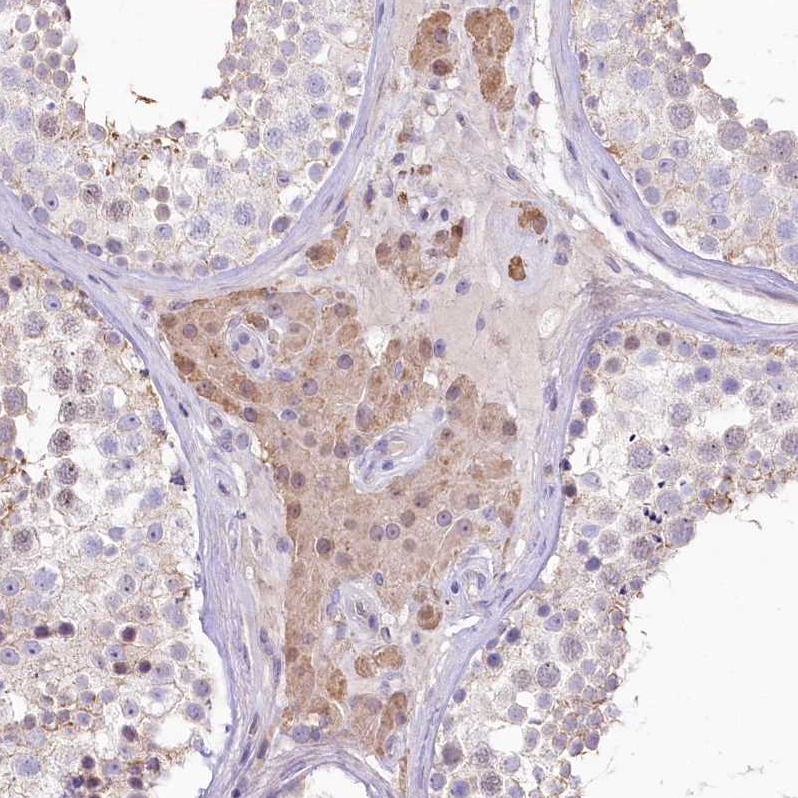

Immunohistochemical staining of human Cerebellum shows strong positivity in processes in cells in molecular layer.